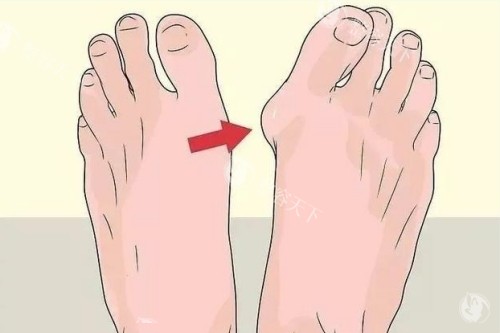

重获美足的喜悦

经过一段时间的改善,我终于可以穿上漂亮的鞋子,自信地行走。看着自己重新变得美观的双脚,心中充满感慨。这次治疗不仅解决了我多年的拇外翻困扰,更让我感受到了正规医疗的价值和温暖。

现在每次穿上喜欢的鞋子,我都会想起这次满意的就医经历。如果你也在为拇外翻问题困扰,不妨去了解一下,或许也能像我一样重获自信的步伐。